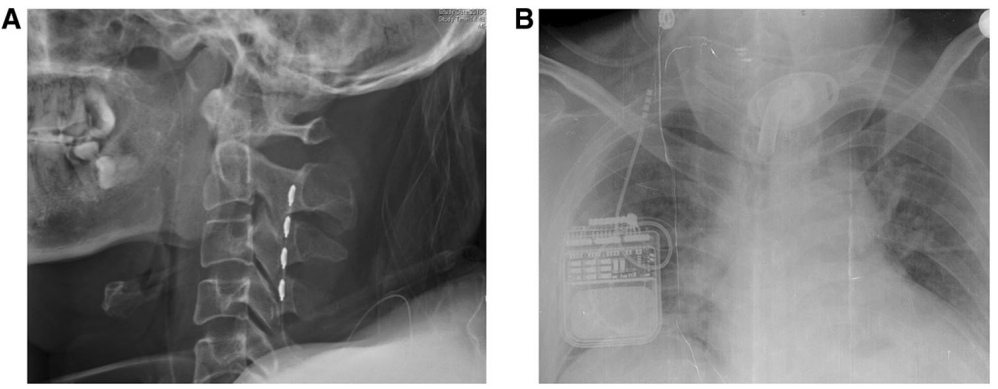

近年来,SCS治疗意识障碍得到越来越多的应用。SCS通过手术放置刺激电极在颈髓C2-C4水平硬膜外正中部,电刺激通过上行性网状结构激活系统及丘脑下部激活系统传达到大脑皮层。